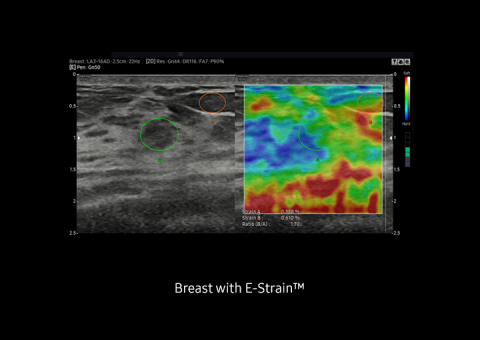

E-Strain™ is designed to enable quick and easy calculation of the strain ratio between two regions of interest for day-to-day practice. Simply by setting the two targets, you can receive accurate, consistent results and make informed decisions in many types of diagnostic procedures.